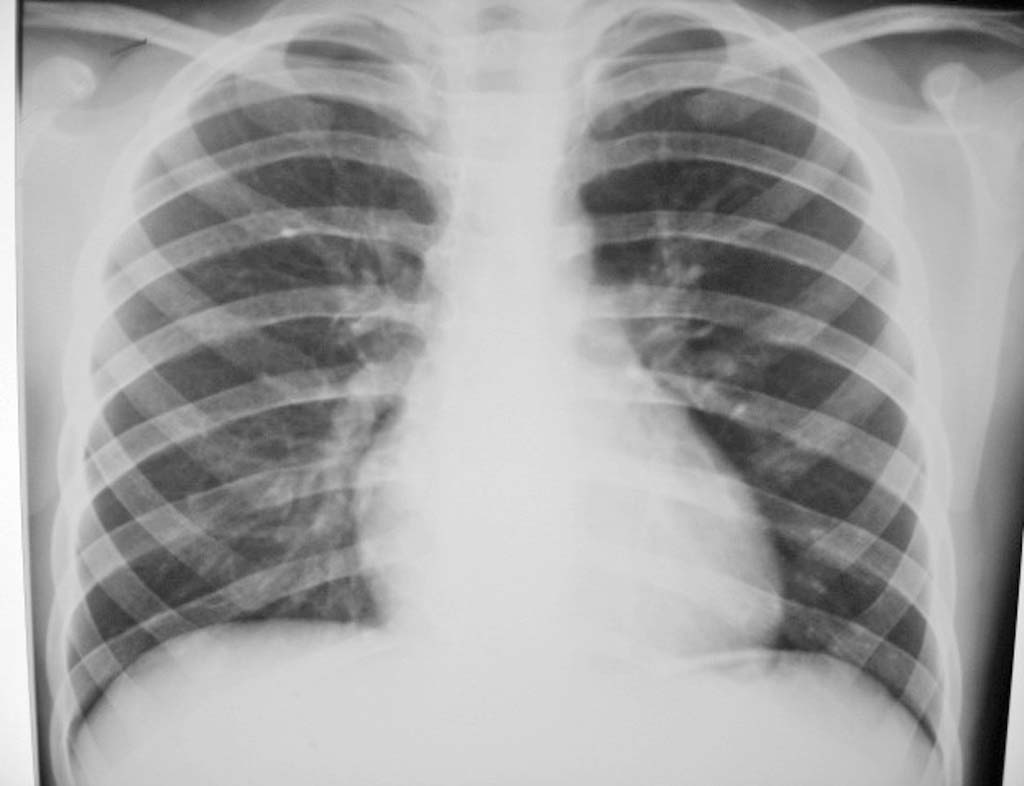

男.8岁.咳嗽发烧3天.咳血样痰2天

胸部平片未见明显异常。可能为急性支气管炎。

支气管炎

提示支气管炎征象。

没见明确异常,可能为上呼吸道的问题,对症治疗后复诊吧

考虑有支扩

右肺中下野中内带可疑囊腔

右下肺野内带有炎症。

支扩